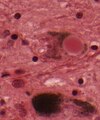

Microscopic

Features:[53]

- Loss of pigmented (catecholaminergic) neurons in the substantia nigra and locus ceruleus.

- Gliosis - due to neuron loss.

- Lewy bodies (in remaining neurons) - key feature.

- Eosinophilic cytoplasmic inclusion with "dense" (darker) core and pale (surrounding) halo.

- Consist of filaments composed of alpha-synuclein.

- Lewy neurites - alpha-synuclein positive processes.